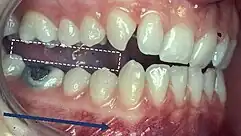

Classification of occlusion and malocclusion plays an important role in diagnosis and treatment planning in orthodontics. In order to describe the relationship of the maxillary molars to the mandibular molars, the Angle’s classification of malocclusion has commonly been used for many years.[8] This system has also been adapted in an attempt to classify the relationship between the incisors of the two arches.[9]

When discussing the occlusion of the posterior teeth, the classification refers to the first molars and may be divided into three categories:

- Class I: The mandibular first molar occludes mesially to the maxillary first molar, with the mesiobuccal cusp of maxillary first molar occluding in the buccal groove of mandibular first molar

- Class II: The mesiobuccal cusp of the maxillary first molar occludes anterior to the buccal groove of the mandibular first molar

- Class III: If the mesiobuccal cusp of the maxillary first molar occludes posterior to the buccal groove of the mandibular first molar[8]

Any deviation from the normal relation of teeth (Class I) is considered a malocclusion.